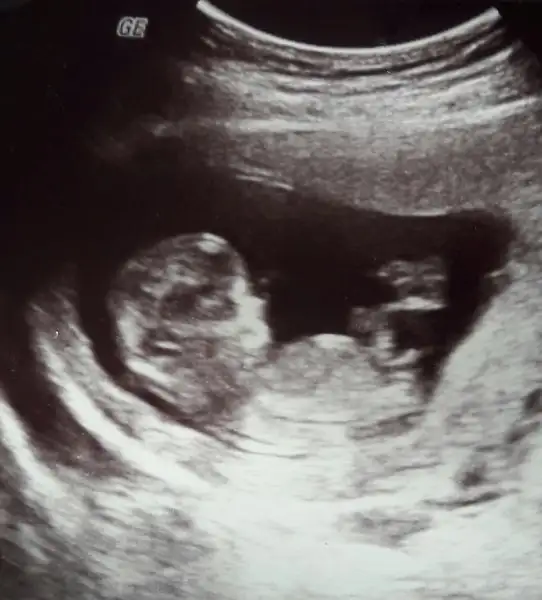

Teyzoşları size fındık kurdumun resmini göstermek istiyorum. Allahım sana şükürler olsun. Rabbim isteyen ve bu yolda emek harcayan herkese nasip etsin inşallah :KK66:

Senin bebiş paralel geliyor ama ucu kalkık gibi tamda karar veremedim ama bu teoriye göre kıza daha benzettim sanki :)

Maşallah ona. Yüzüde belirginleşmiş. Ağzı yüzü kutu gibi.. Çok tatlı. Eşim telefona bakarken soruyor napıyosun diye, bebeğimin arkadaşlarının annesiyle konuşuyorum diyorum. Kimbilir belki bebişlerin yolu kesişir bir yerde.:KK49::KK46: